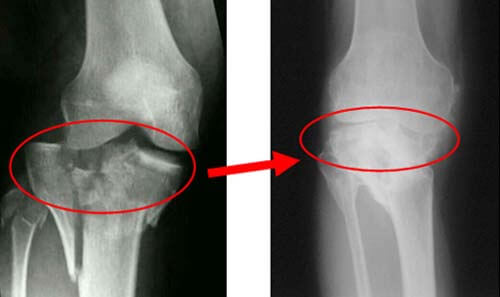

Больной сустав со временем начнет менять форму. Если сделать на ранних этапах болезни рентгеновский снимок, то аномалию можно будет выявить.

Диагностика коленного сустава стала намного проще благодаря современному медицинскому оборудованию, а разработанные профессиональными врачами методики помогают остановить развитие болезни и помочь пациентам обрести утраченную привычную подвижность.

С помощью УЗИ можно определить состояние мышц и связок, суставов и сухожилий. Рентгеновский снимок расскажет, есть ли изменения суставного хряща. С помощью сцинтиграфии врач может определить наличие нарушений метаболизма в тканях.